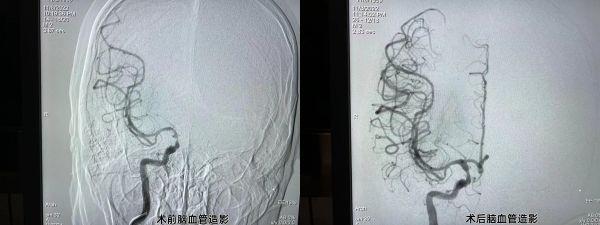

脑血管造影术前、术后对比 。

就这样 , 一场与时间赛跑的“接力赛”正式打响 , 两支不同的专业团队医生 , 同时上台介入手术 。 当日20时许 , 该院胸痛中心负责人、心血管内科主任邓昭武带领胸痛团队为李先生进行了冠状动脉造影 , 发现右侧冠状动脉中远段闭塞 , 立即行冠状动脉球囊扩张术+支架植入术;22时 , 朱灿敏带领卒中中心团队进行“接台” , 并随即为李先生行全脑血管介入手术 , 脑血管造影见:右侧颈内动脉末端次全闭塞 , 血栓形成;右侧大脑前动脉闭塞 。 立即行颅内动脉取栓术;23时30分 , 李先生手术成功结束 , 安全转回神经内科病房 。